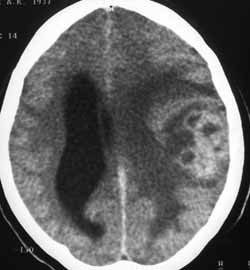

Справа - множественные абсцессы левой височной доли. По КТ-картине и клинически (болеет 7 месяцев с постепенным нарастанием неврологических растройств) предполагалась глиальная опухоль.